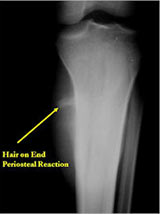

Plain X-Rays:

- Diaphyseal lesion on external surface of bone; medullary canal uninvolved

- Radiolucent mass extending into surrounding soft tissues

- Saucerized cortex with chondroblastic soft tissue mass that is usually primarily radiolucent on plain X-rays

- Periosteal reaction usually most evident feature on surface of bone (Hair on End or Sunburst appearance with spiculated pattern of calcification oriented perpendicular to the bone)

- Cortical thickening at margins of erosion (40%)

- Rarely may have Codman’s triangle

- Spiculated or sunburst periosteal reaction (due to periosteal elevation)